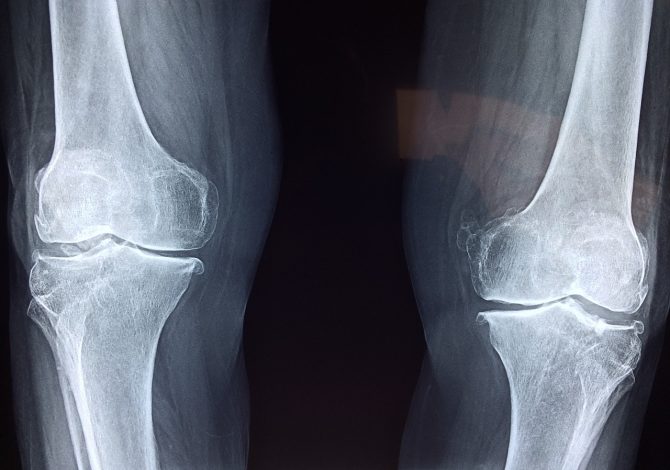

L’acido ialuronico è una sostanza che si trova naturalmente nelle articolazioni, oltre che in altre parti del nostro corpo, e serve a rendere viscoso il contatto tra le ossa e le cartilagini, e tra le cartilagini stesse, favorendo il movimento articolare. Tuttavia per l’età o per usura le cartilagini tendono ad assottigliarsi, provocando dolore e limitazione di movimento tipici dell’artrosi, ed è in questi casi che si sente parlare di infiltrazioni di acido ialuronico. Rimanendo nell’ambito dello sport sono spesso le ginocchia a essere interessate alle infiltrazioni, ma non sono le uniche.

Le infiltrazioni di acido ialuronico per gli sportivi sono una terapia già conosciuta dagli anni Settanta del secolo scorso, e in tutti questi decenni la loro efficacia è stata scientificamente più volte confermata: non si tratta di una tecnica risolutiva del problema ma di un trattamento conservativo dell’artrosi, in particolare delle ginocchia (gonartrosi), dell’anca (coxoartrosi), dell’articolazione tra polso e mano (Rizoartrosi) o della spalla. Tecnicamente si tratta di iniezioni intra-articolari di sodio ialuronato chiamate anche viscosupplementazioni, perché la sostanza iniettata ha proprietà viscoelastiche esattamente pari all’acido ialuronico già presente nelle articolazioni e nel liquido sinoviale. Le infiltrazioni servono quindi a ristabilire le naturali condizioni di viscosità articolare, ristabilendo la naturale mobilità articolare ed eliminando la condizione che genera dolore.

Ovviamente solo quando è un medico ortopedico a prescriverle in base all’analisi della condizione dell’articolazione. Tipicamente vengono prescritte nei casi di assottigliamento della cartilagine che ricopre le estremità delle ossa per evitare interventi più invasivi come quelli chirurgici, e nella stragrande maggioranza dei casi riguardano le articolazioni che sorreggono il peso del corpo, come appunto le ginocchia e l’anca.